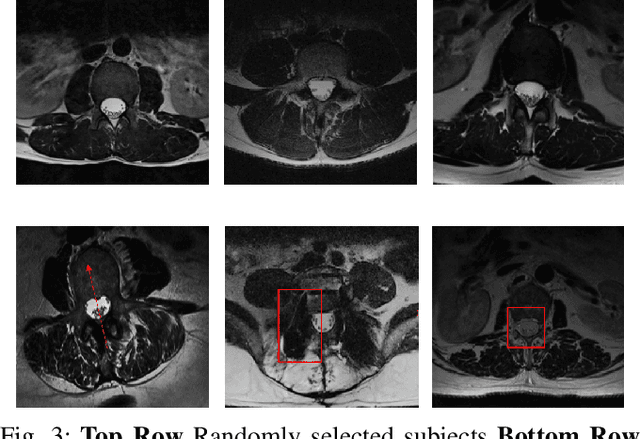

Abstract:Yes, it can. Data augmentation is perhaps the oldest preprocessing step in computer vision literature. Almost every computer vision model trained on imaging data uses some form of augmentation. In this paper, we use the inter-vertebral disk segmentation task alongside a deep residual U-Net as the learning model, to explore the effectiveness of augmentation. In the extreme, we observed that a model trained on patches extracted from just one scan, with each patch augmented 50 times; achieved a Dice score of 0.73 in a validation set of 40 cases. Qualitative evaluation indicated a clinically usable segmentation algorithm, which appropriately segments regions of interest, alongside limited false positive specks. When the initial patches are extracted from nine scans the average Dice coefficient jumps to 0.86 and most of the false positives disappear. While this still falls short of state-of-the-art deep learning based segmentation of discs reported in literature, qualitative examination reveals that it does yield segmentation, which can be amended by expert clinicians with minimal effort to generate additional data for training improved deep models. Extreme augmentation of training data, should thus be construed as a strategy for training deep learning based algorithms, when very little manually annotated data is available to work with. Models trained with extreme augmentation can then be used to accelerate the generation of manually labelled data. Hence, we show that extreme augmentation can be a valuable tool in addressing scaling up small imaging data sets to address medical image segmentation tasks.